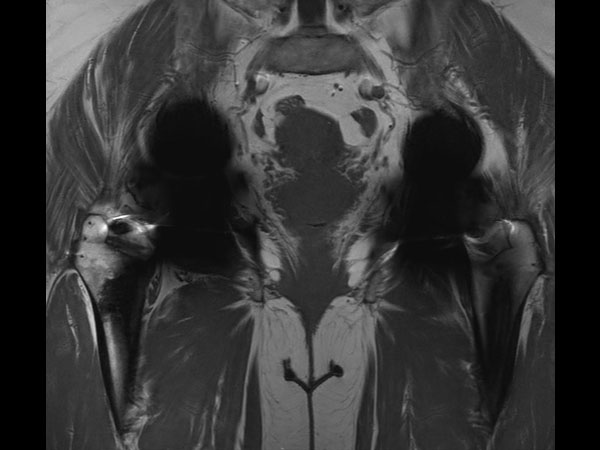

Coronal T1w MARS